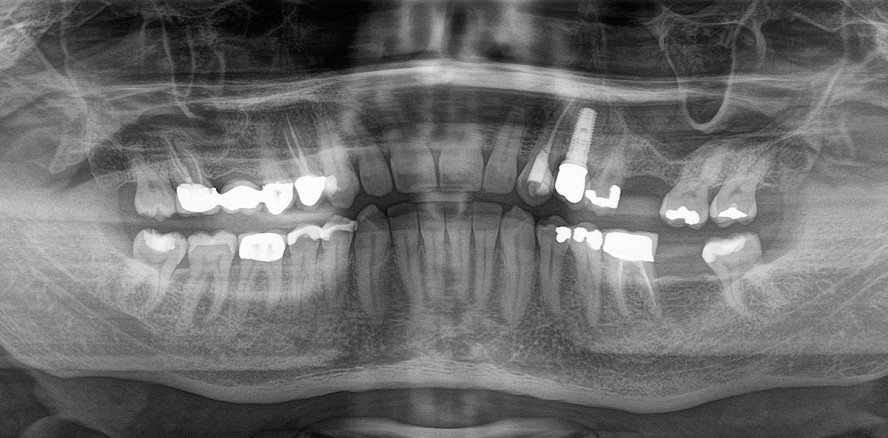

Seit über zehn Jahren sind 3-D-Röntgenaufnahmen in der Zahnmedizin möglich. In Kombination mit der neuen Endodontie-Software 3D Endo™ (Dentsply Sirona) bietet diese Art der Bildgebung einen noch größeren Mehrwert für die Planung der Wurzelkanalbehandlung.

Die Einführung der digitalen (dentalen) Volumentomografie in die tägliche Praxis hat in der Zahnmedizin und besonders bei der endodontischen...

In der modernen Endodontie erleichtern bildgebende Verfahren zunehmend die Diagnosestellung und Analyse der individuellen Situation im Kanal....